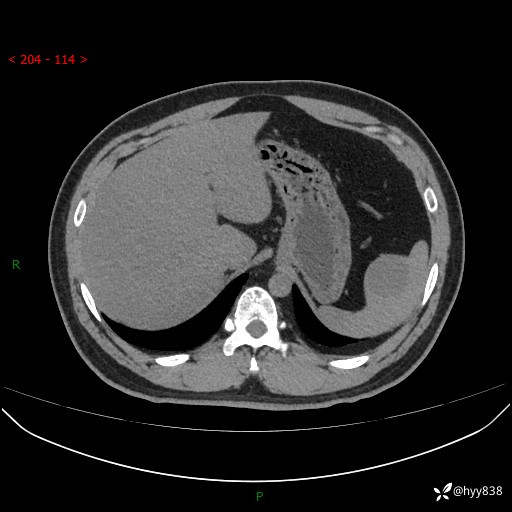

【患者信息】:31岁/男

【主诉】:超声发现脾脏肿物,为进一步诊治来我院,门诊以“脾脏占位”收入院

【检查】:上腹部CT平扫+增强